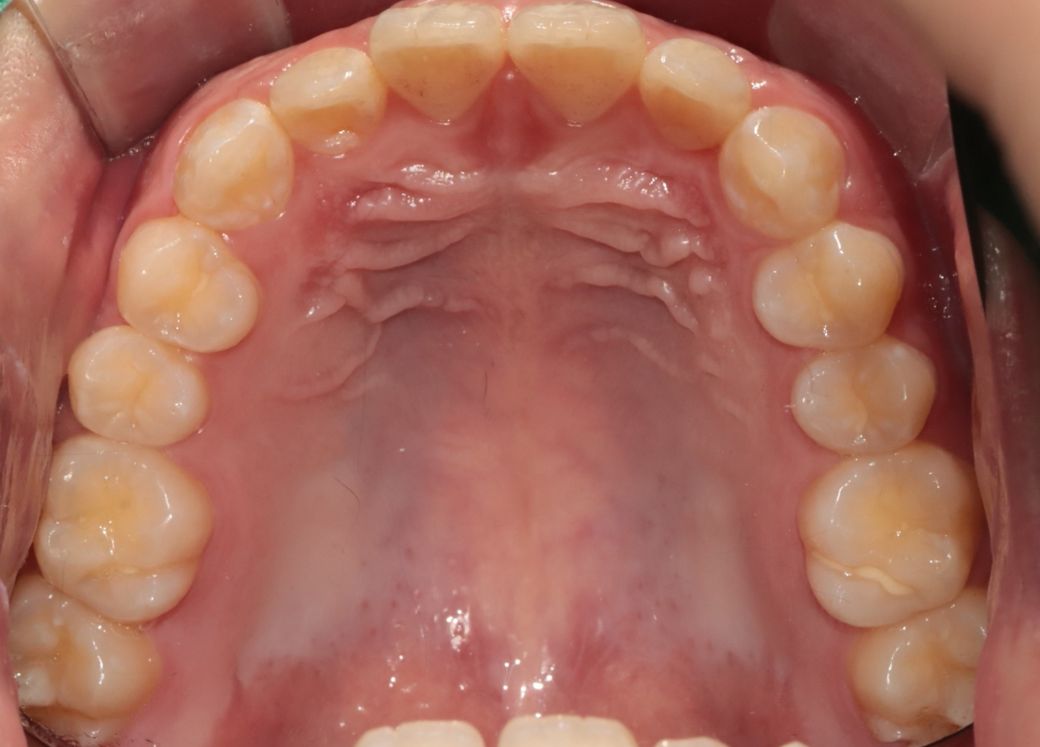

• 1번 째 사진

사진으로 보이는 상악치아의 경우에는 가지런해 보입니다

돌출입이 치아자체의 위치의 문제라면 교정으로 넣을수 있지만 골격적인 문제라면 교정이외에 추가적인 치료등이 필요할수 있습니다.